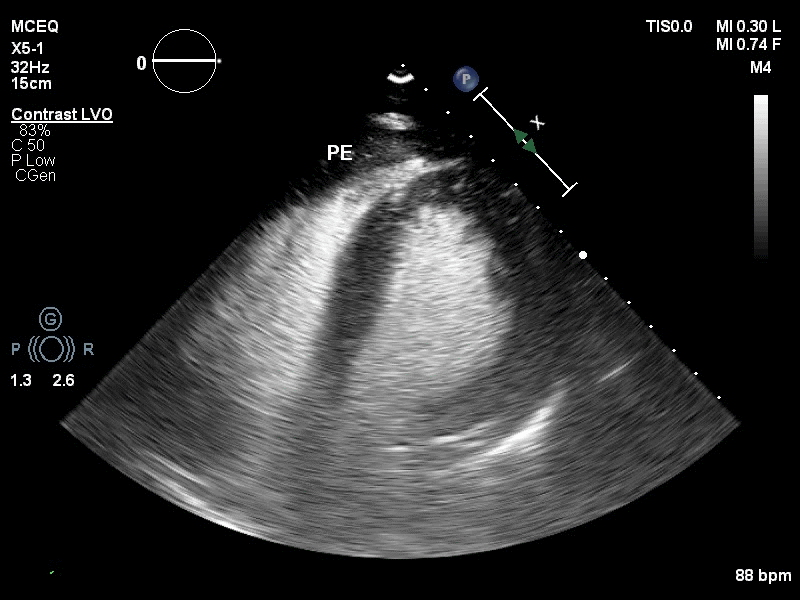

为进一步明确诊断,行床旁心脏超声造影,可见Contrast-LVO模式下,可见心包腔内可见由左室心尖缓慢飘出的点状造影剂声像。

(视频2)

视频2 -3 : Contrast-Low MI模式下,心包腔内亦可见少量的造影剂回声。